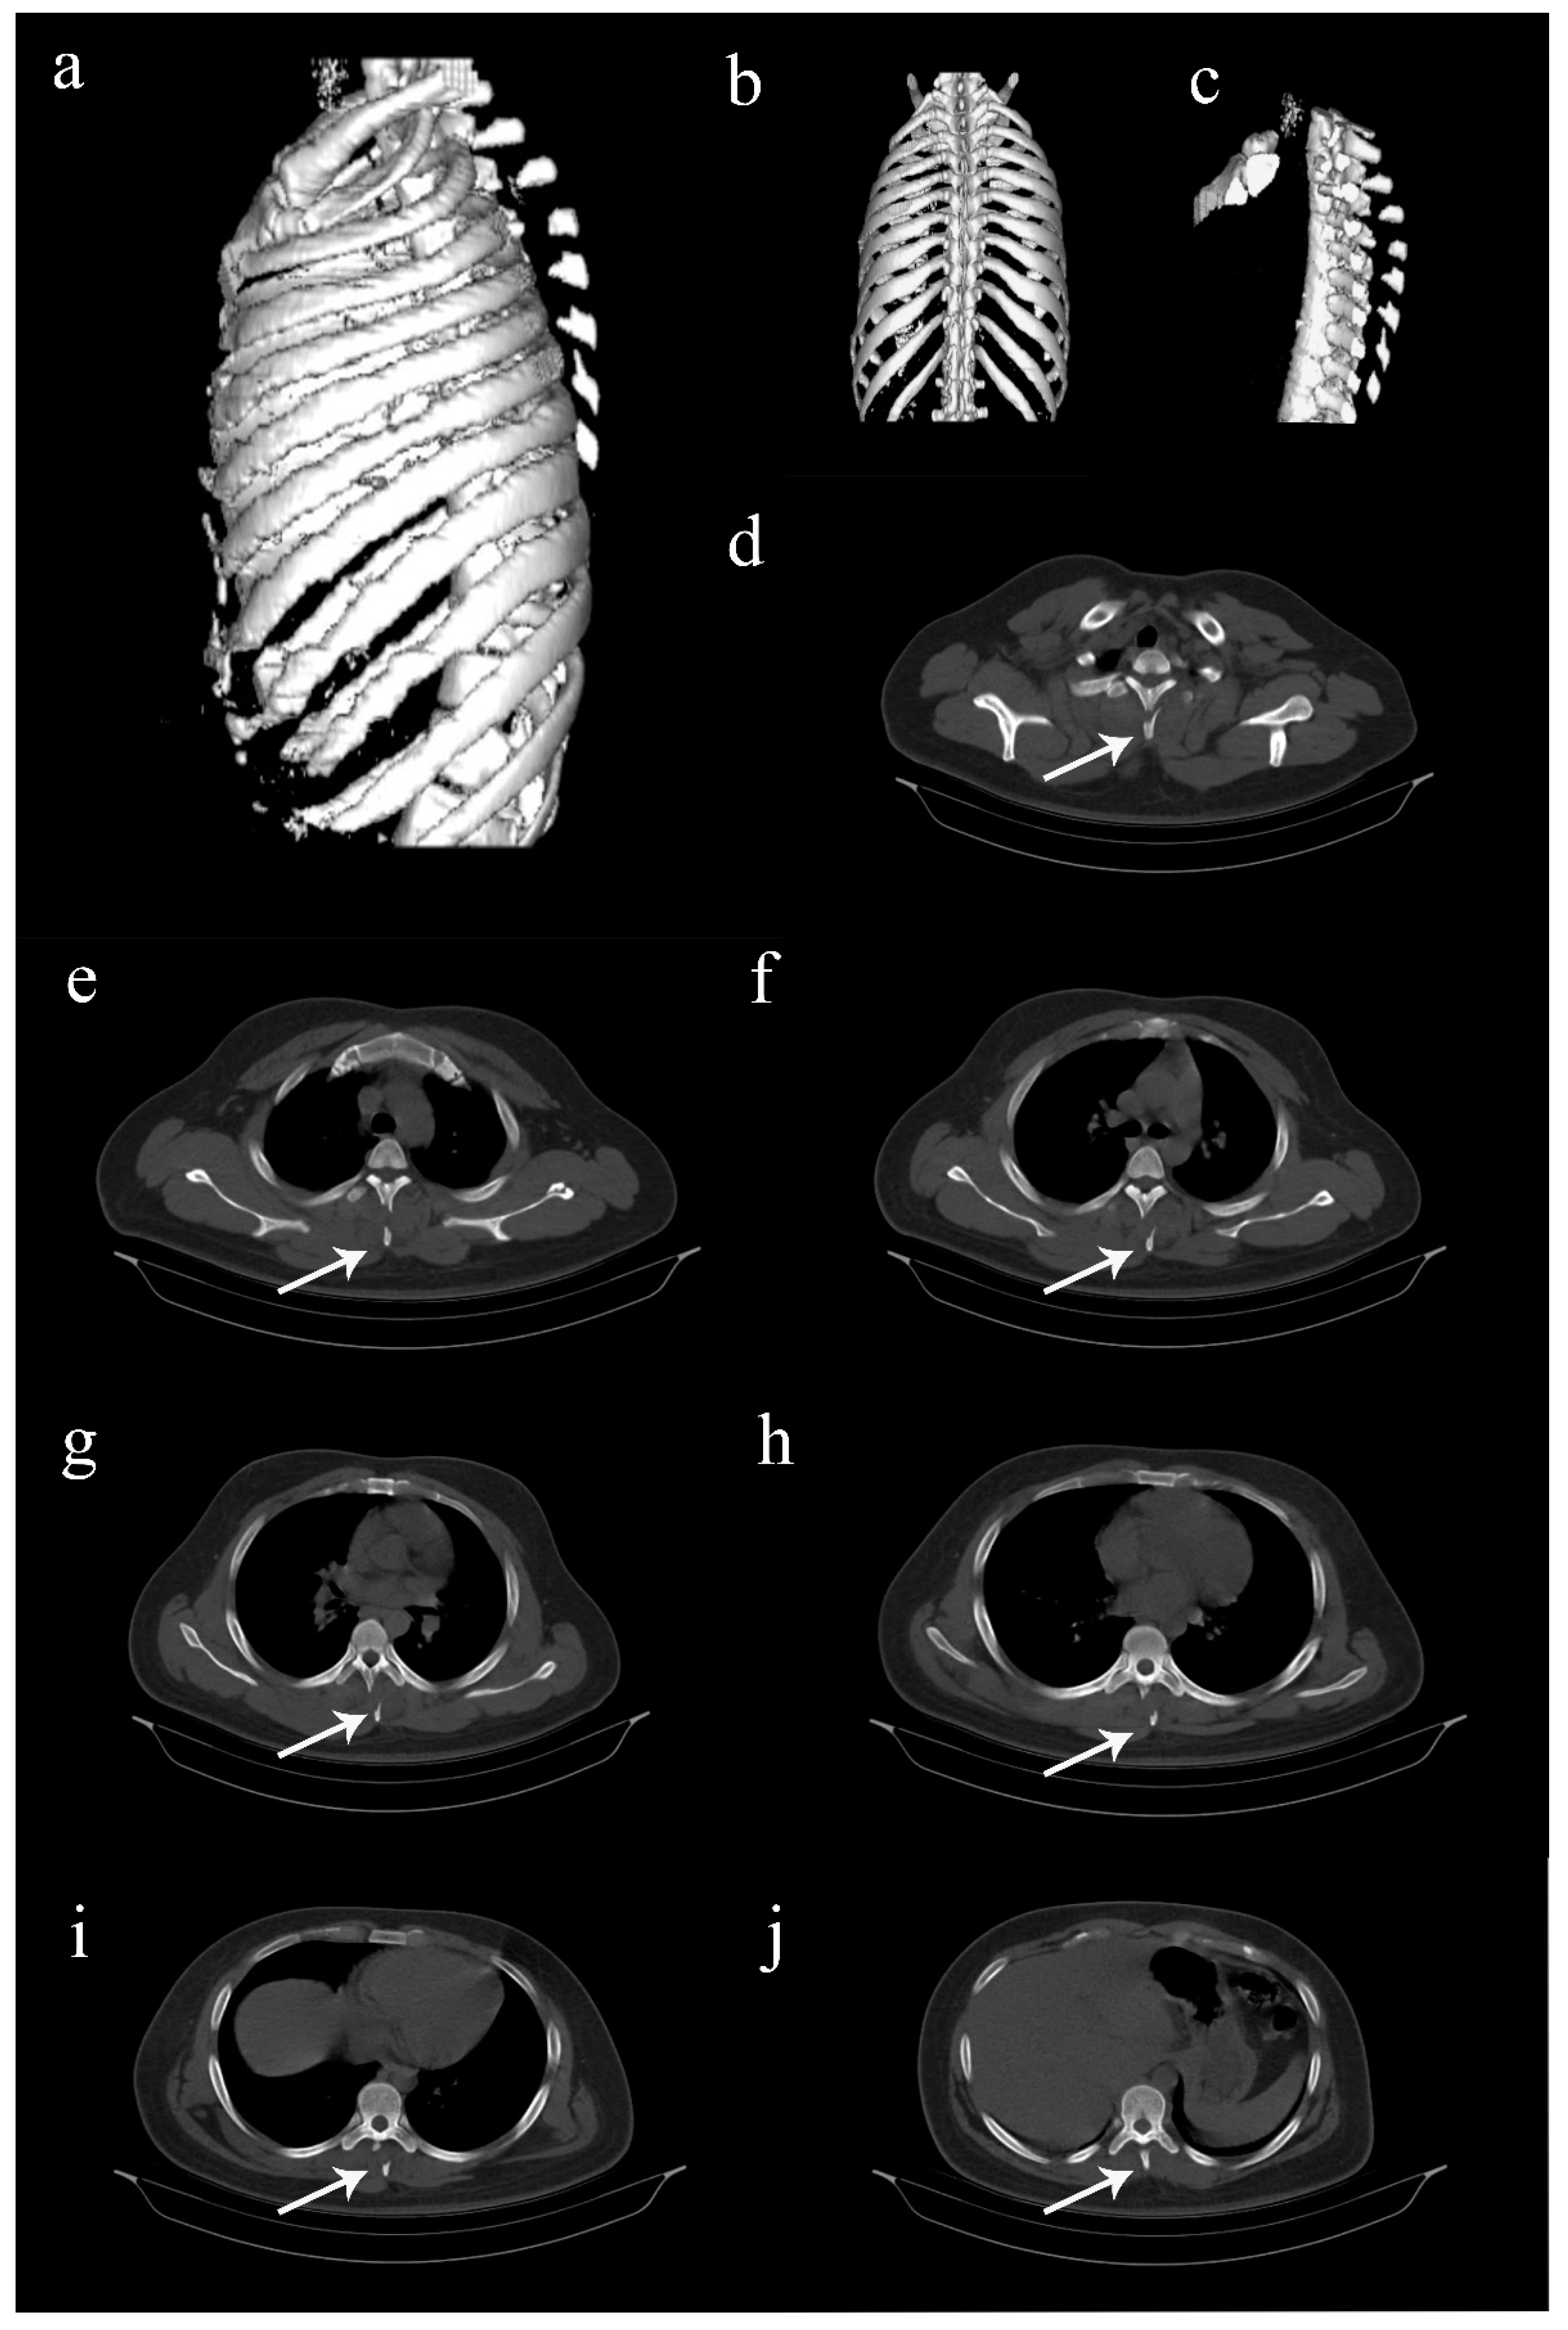

Figure 2. Computed tomography (CT) images of the thoracolumbar spine. (ac) Three-dimentional reconstructed CT images showing multiple spinous process fractures extending from T2 to T8 levels, resembling clay shoveler’s fractures [1,2,3,4,5]. (dj) Axial view CT images extending from T2 to T8 levels, showing the fractured spinous processes (arrows). Such involvement of multiple spinous processes in the thoracic spine is rare, and hence, sparsely reported [1,2,3]. Considering the stability of these fractures, it was decided to treat the patient conservatively. He was put on a thoracolumbar corset and was advised adequate bed rest for two weeks. Analgesics were provided, and self-care for the abrasions was taught. Protected weight bearing and mobilization exercises were started on the second week while on thoracolumbar corset support. The recovery was quick, and the patient was back to his full functional status by 6 weeks. Further follow-up was uneventful.